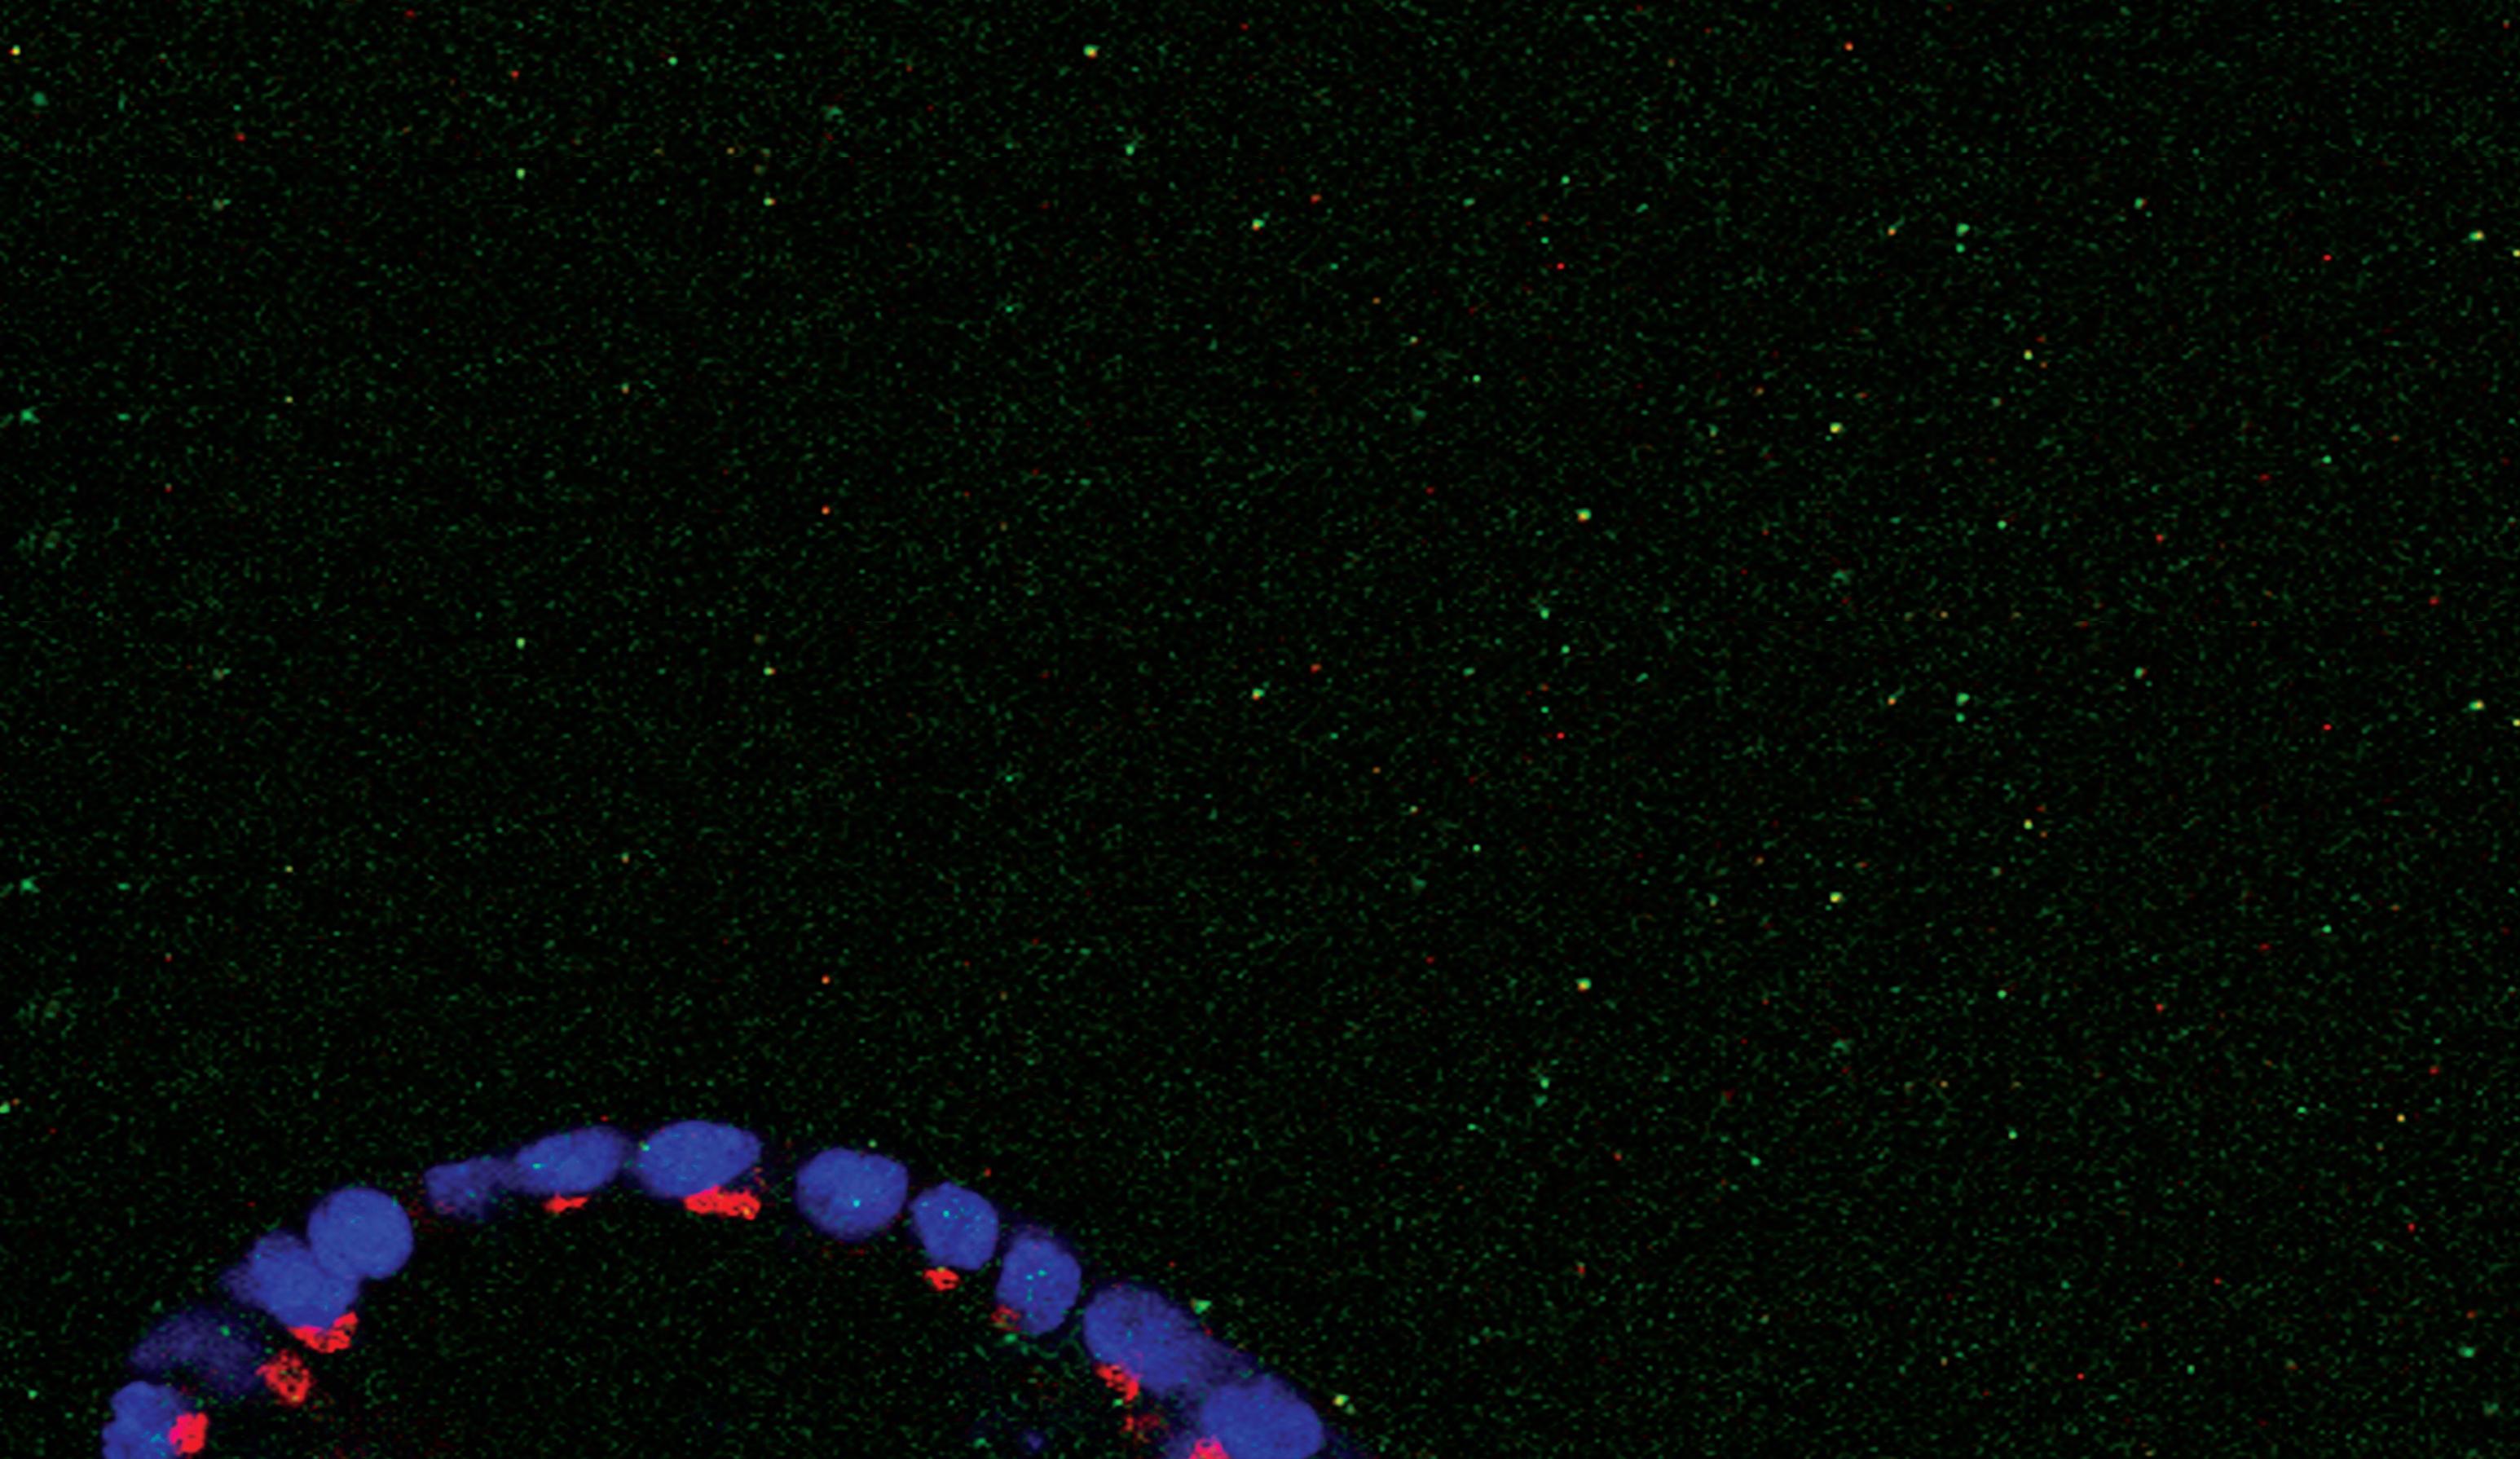

About our cover Healthy Tissue this image was obtained by laser scanning confocal microscopy of normal human mammary epithelial cell colonies cultured in three-dimensional in vitro conditions. Provided by the tisch Cancer institute laboratory of eduardo f farias, Phd, assistant Professor, Mount sinai school of Medicine.